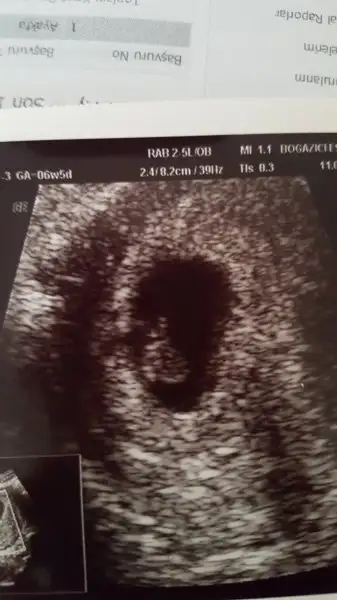

7+3 lük karından ultrason görüntüm bu şekildedir. Hem kesenin şekline hem de bebişin duruşuna göre yorum yaparsanız sevinirim. Tşk.